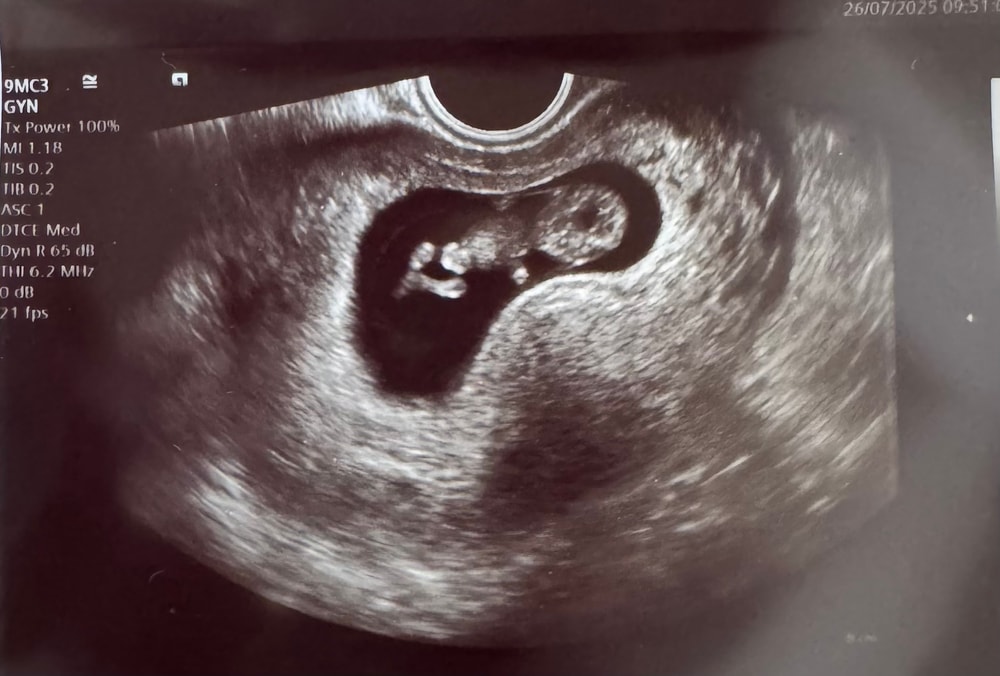

Была сегодня на УЗИ)

Ставят срок по УЗИ 10+2

Акушерский срок 9+4 - 9+6

Человек копошился, шевелил ручками и ножками🥰